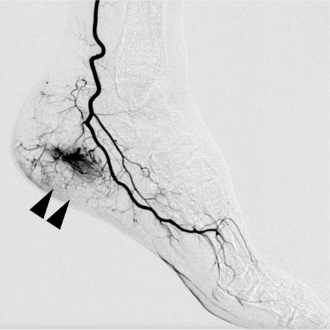

「モヤモヤ血管」とは、慢性的な痛みやこりの原因となる「異常な炎症血管」をわかりやすく表現した呼び方です。血管造影検査で見ると、この血管がモヤモヤとした状態で写っているため、このような名前が付けられました。

動注療法では、エコーを使用して手関節または足関節付近の動脈に細い針を刺し、溶けにくい薬液を注入します。この薬液が「モヤモヤ血管」のみを減らし、痛みを取り除くことを目的としています。

※症例の提供:オクノクリニック様